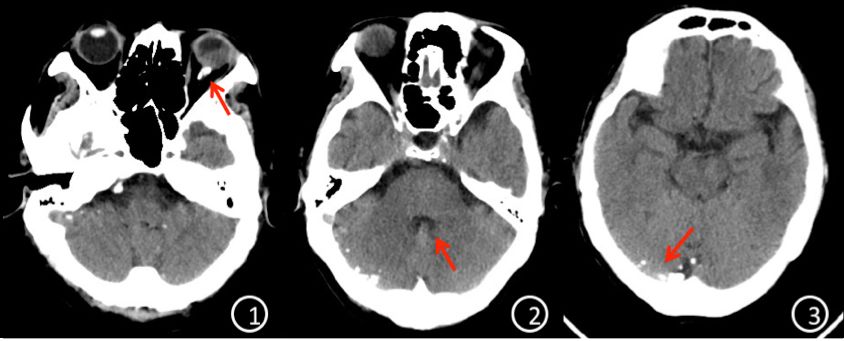

入院完善检查后,局麻下行“左眼脱位晶状体超声粉碎+后段玻璃体切割+眼内探查+重水+眼内光凝+气液交换术”。术中切除脱位晶状体周围玻璃体,超声粉碎吸除脱位晶体,切除所有玻璃体和积血,见颞下方及颞上方视网膜裂孔,视网膜隆起高,注入重水4ml,视网膜平伏。再行视网膜裂孔激光光凝,气压35mmHg气液交换,置换重水。准备缝合巩膜和结膜切口时,患者突发胸闷不适,随即呼之不应,血氧饱和度低,血压下降,考虑休克、呼吸衰竭。立即心肺复苏抢救,气管插管和机械通气,查肺动脉CT(CTPA):双侧胸腔积液伴肺膨胀不全,未见肺动脉栓塞;头颅CT提示:颅内积气,左侧眼球、小脑幕、第三脑室、中脑导水管及第四脑室内多发高密度影。结合患者病史和影像学资料,诊断为“眼内重水迁移入脑室”(图1)。立即转入ICU予以对症生命支持,同时行体外膜肺氧合术(ECOM)。ECOM持续4天后,患者神志转清。

图1. ①头颅CT平扫显示枕叶蛛网膜下腔高密度影,提示重水沉积于枕叶蛛网膜下腔;②显示重水蓄积于第四脑室。

图4. ①头颅CT平扫红色箭头提示眼眶内仍有重水残留;②四脑室已无重水蓄积;③仍有少量重水蓄积于枕叶蛛网膜下腔。